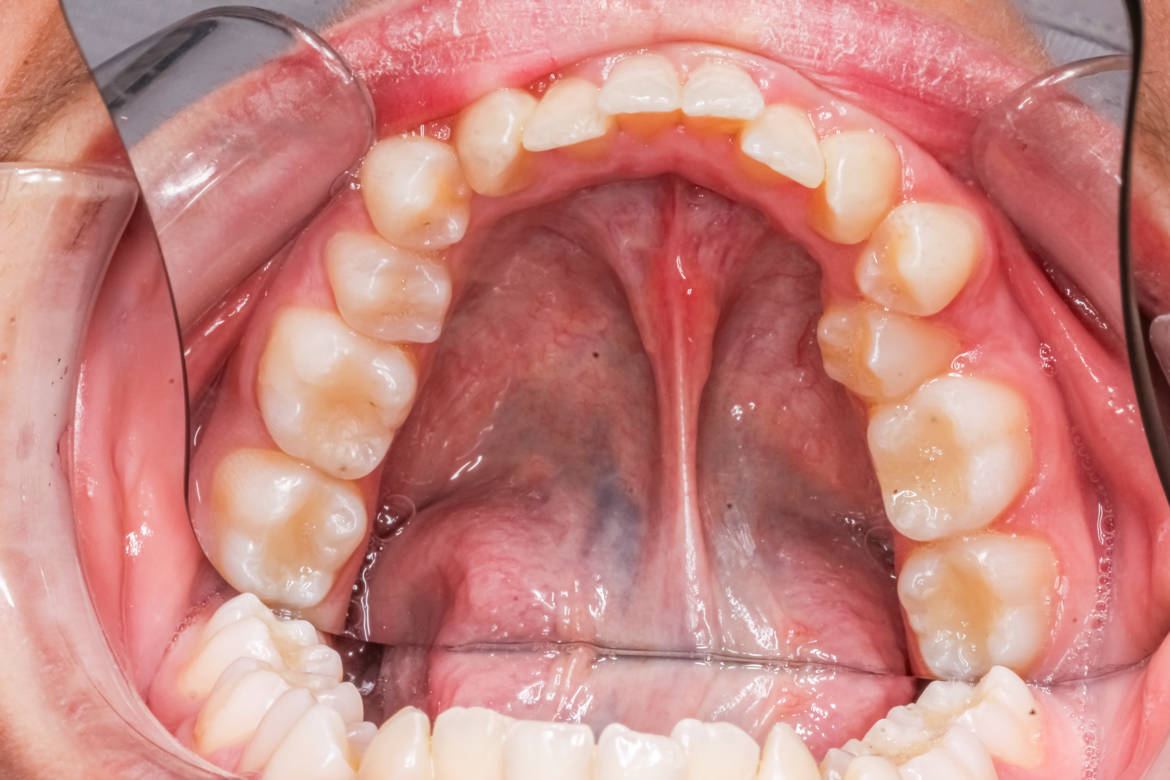

Cette intervention consiste en la section du frein de langue, ce petit bout de tissu qui relie la langue au plancher de la bouche. Notamment pour tenter de faciliter l’allaitement et diminuer les douleurs de la maman. Suite à la prise de position de l'Académie médicale de France sur ce sujet, les HUG ont publié un article en ligne pour tenter d’expliquer que la décision d'une frénotomie n'est pas anodine et que les études sur le sujet restent insuffisantes.